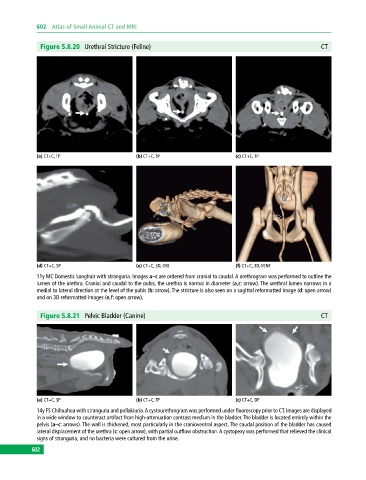

Figure 5.8.20 Urethral Stricture (Feline) CT

(a) CT+C, TP (b) CT+C, TP (c) CT+C, TP

(d) CT+C, SP (e) CT+C, 3D, OBL (f) CT+C, 3D, VENT

11y MC Domestic Longhair with stranguria. Images a–c are ordered from cranial to caudal. A urethrogram was performed to outline the

lumen of the urethra. Cranial and caudal to the pubis, the urethra is normal in diameter (a,c: arrow). The urethral lumen narrows in a

medial to lateral direction at the level of the pubis (b: arrow). The stricture is also seen on a sagittal reformatted image (d: open arrow)

and on 3D reformatted images (e,f: open arrow).

Figure 5.8.21 Pelvic Bladder (Canine) CT

(a) CT+C, SP (b) CT+C, TP (c) CT+C, DP

14y FS Chihuahua with stranguria and pollakiuria. A cystourethrogram was performed under fluoroscopy prior to CT. Images are displayed

in a wide window to counteract artifact from high‐attenuation contrast medium in the bladder. The bladder is located entirely within the

pelvis (a–c: arrows). The wall is thickened, most particularly in the cranioventral aspect. The caudal position of the bladder has caused

lateral displacement of the urethra (c: open arrow), with partial outflow obstruction. A cystopexy was performed that relieved the clinical

signs of stranguria, and no bacteria were cultured from the urine.